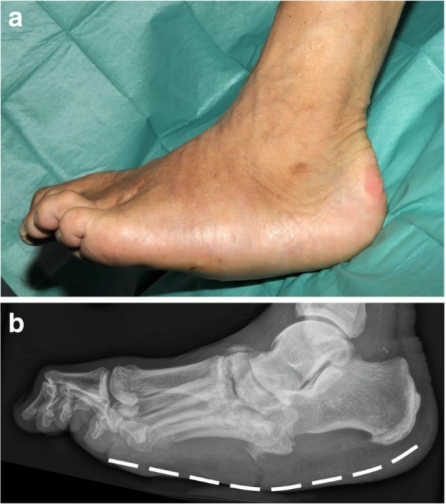

摇椅足畸形是Charcot足末期的典型表现